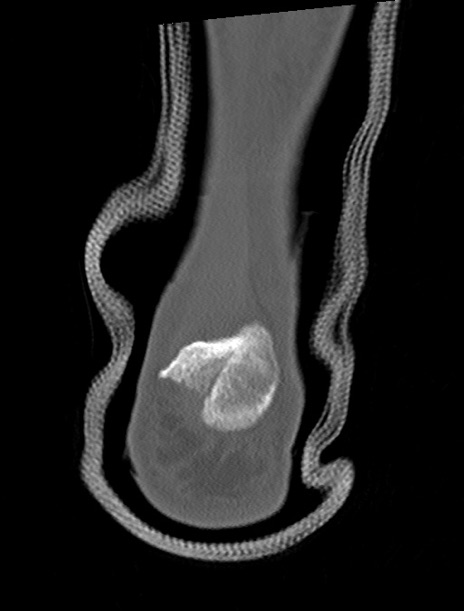

症例37 左足関節CT(冠状断像)

左足関節CT

矢状断像